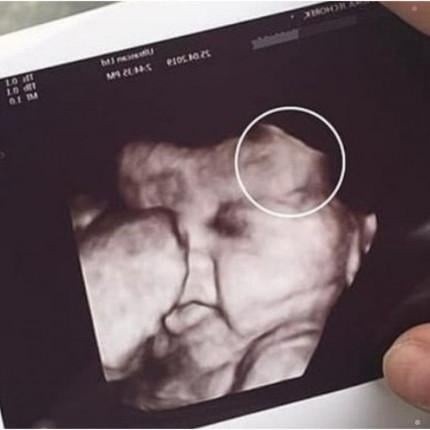

Doctors later explained that the initial scan had displayed an unexpected shape next to the developing baby, prompting the need for additional imaging. After a follow-up exam, they determined it was a benign artifact—a harmless visual distortion caused by the baby’s position and the machine’s angle. The clarification brought immense relief to both women, who had been preparing themselves for difficult news.

The family later expressed gratitude to the clinic for handling the situation with care and transparency. Medical specialists remind expecting parents that unusual ultrasound images are not uncommon and often resolve with clearer scans. The incident underscores the emotional weight of prenatal appointments and the importance of compassionate communication in moments of uncertainty.READ MORE BELOW